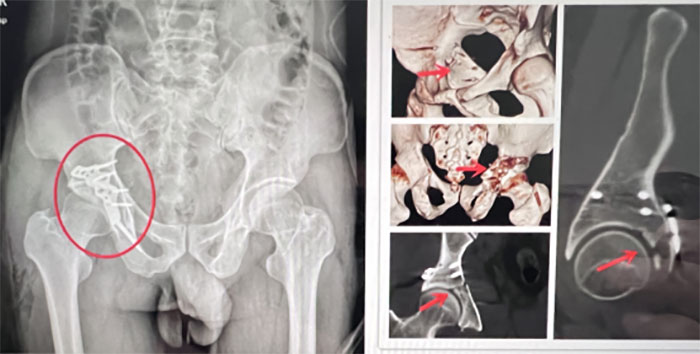

3D打印模型

術前鋼板預彎

經(jīng)過術前模擬,創(chuàng)傷骨二科(骨八科)團隊決定應用Stoppa入路微創(chuàng)實施骨盆骨折切開復位內(nèi)固定術——這是一套能夠降低手術風險、提高手術精確性的治療方案。憑借術前的精準模擬,創(chuàng)傷骨二科(骨八科)團隊1小時即完成了這臺復雜的骨盆手術,術中出血僅200ml。術后,許女士未發(fā)生任何神經(jīng)并發(fā)癥,輔助康復治療后恢復良好。

術后效果